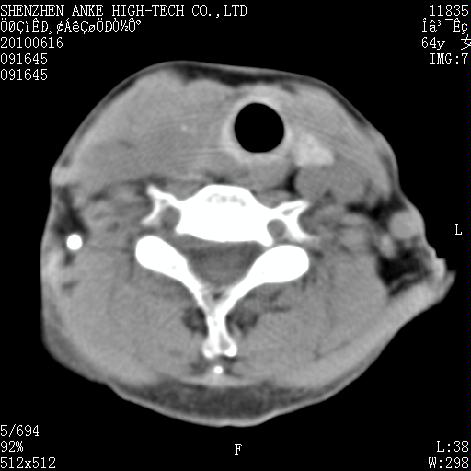

标题: CT27132:患者女,64岁,颈部及全身多处包块,现觉吞咽困难4 [打印本页]

标题: CT27132:患者女,64岁,颈部及全身多处包块,现觉吞咽困难4

右侧甲状腺癌伴右颌下腺淋巴结转移

右侧甲状腺癌伴淋巴结转移

淋巴瘤可能,再向下扫描胸部看纵隔内淋巴结

右侧甲状腺癌伴右颌下腺淋巴结转移!建议增强!